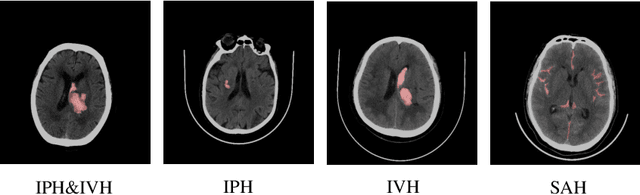

Abstract:Hemorrhagic Stroke (HS) has a rapid onset and is a serious condition that poses a great health threat. Promptly and accurately delineating the bleeding region and estimating the volume of bleeding in Computer Tomography (CT) images can assist clinicians in treatment planning, leading to improved treatment outcomes for patients. In this paper, a cascaded 3D model is constructed based on UNet to perform a two-stage segmentation of the hemorrhage area in CT images from rough to fine, and the hemorrhage volume is automatically calculated from the segmented area. On a dataset with 341 cases of hemorrhagic stroke CT scans, the proposed model provides high-quality segmentation outcome with higher accuracy (DSC 85.66%) and better computation efficiency (6.2 second per sample) when compared to the traditional Tada formula with respect to hemorrhage volume estimation.